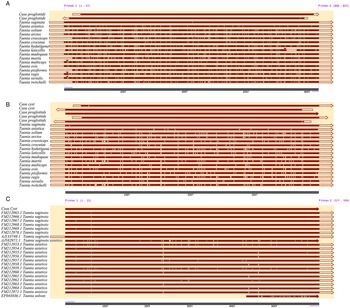

The routine laboratory blood tests, including eosinophil and lymphocyte count, were completely normal apart from the elevated inflammation markers (C-reactive protein and neutrophil count). Schistosomes, Clonorchis sinensis, Echinococcus granulosus and Toxoplasma gondii antibodies were negative in his serum, as were Cryptococcus capsular antigen and next-generation sequencing results from cerebrospinal fluid. Multiple intracranial nodules affecting the supratentorial and infratentorial cerebral parenchyma were shown in detail on CT and MRI of the head, indicating possible intracranial parasitic infection (Fig. 1). Ultrasound scan confirmed the presence of 2 palpable and soft masses located in muscles, which were approximately 19 × 8 × 15 mm3 under the right chest wall and 26 × 10 × 19 mm3 under the right midaxillary line (Fig. 2). A subsequent biopsy of the mass (Fig. 3) showed larval-like tissue, peripheral fibrous tissue hyperplasia, lymphocytic infiltration and hyaline degeneration. The patient was probably diagnosed with taeniasis and cysticercosis and treated with oral albendazole (400 mg, twice daily) over 2 weeks. Hydrocortisone 50 mg was provided 2 days after the first albendazole treatment to counteract any potential negative effects on the central nervous system. After only 2 days of this antiparasitic treatment, the adult tapeworm was eliminated through the patient's feces (Fig. 3). When compared with the first MRI (half a month before antiparasitic treatment), the second MRI (half a month after antiparasitic treatment) demonstrated a slightly smaller focus (Fig. 1). The headache and vomiting resolved, and the patient remained symptom free over a 3-month follow-up period.

Fig. 1. MRI shows that the largest cystic nodule was located next to the left ventricular triangle: (A–C) half a month before antiparasitic treatment and (D–F) half a month after antiparasitic treatment.